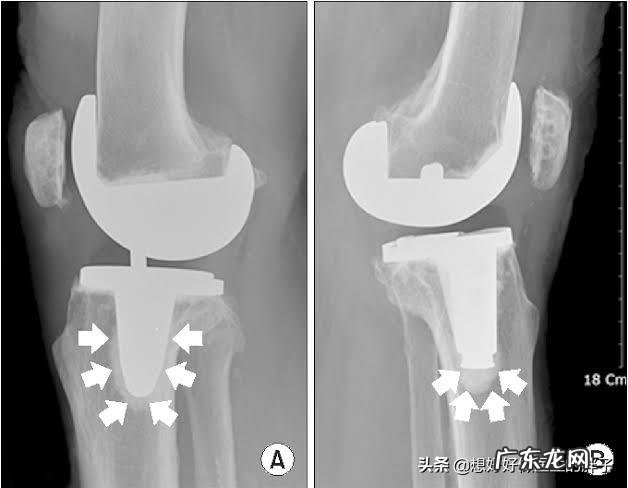

但是如果磨损进一步的加重,那么就会出现软骨的剥脱碎裂,患者的疼痛可能就会越来越严重,在此阶段的患者通常会走平路的时候,也会有明显的疼痛,做x线检查,基本会发现关节间隙已经开始出现了狭窄,而且会有骨赘也就是骨刺的形成 。

当病程进行到了晚期,患者关节间隙会越来越严重,关节也会随之出现明显的变形,有的老年人会出现明显的o型腿,或者是x型腿的改变,基本都是源自于关节内软骨的磨损,导致的关节畸形 。而患者呢,也会出现明显的关节疼痛,严重影响患者的生活质量,有一些患者会出现明显的夜间痛以及休息痛 。